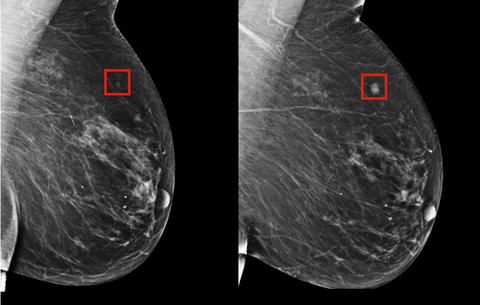

Egy nemzetközi kutatócsoport átfogó képet festett a melldaganatok trendjei és egy adott ország fejlettségének kapcsolatáról. Adataik óriási szakadékot mutatnak a túlélési arányokban, attól függően, ki, hol él.